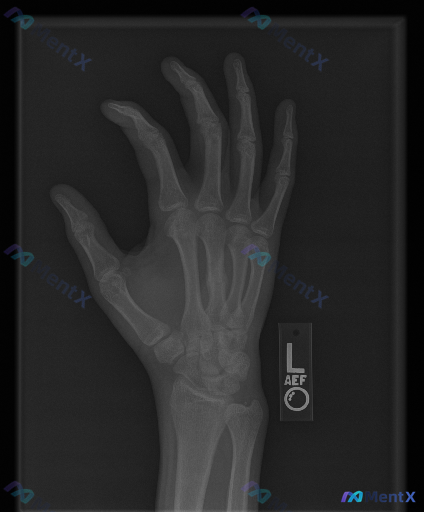

整理到一组影像资料和配套的分析背景,想和大家讨论下这种情况的思路: - 影像来源:左手正位X光片 - 常规阅片所见: - 各腕骨、掌骨、指骨骨皮质轮廓尚完整,未见明显骨折线、脱位或半脱位; - 骨密度、关节间隙未见明显异常; - 关节面、软骨下骨、软组织影也未见明确的典型异常改变(如骨赘、弥漫肿胀、...